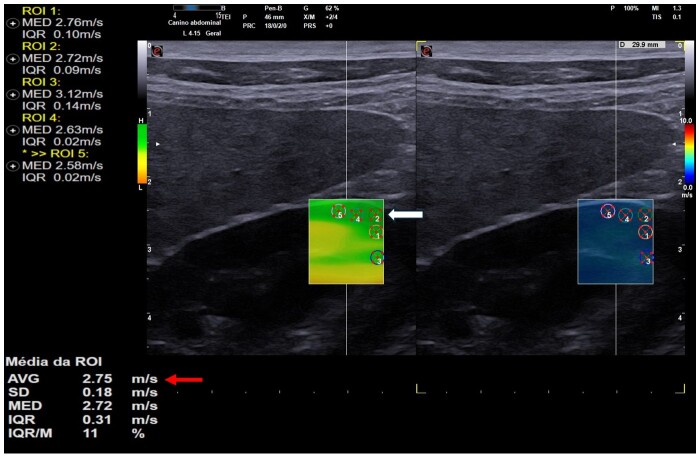

This study evaluated the effects of exposure to tobacco smoke on the kidneys of household dogs using B-mode ultrasonography and Shear-wave Elastography (SWE). Fifteen adult dogs were analyzed and divided into two groups: one exposed to passive smoking for at least two years (n=7) and another non-exposed group (n=8), both without a history of kidney disease. The animals underwent clinical evaluation and laboratory tests, followed by B-mode ultrasonography and renal elastography. Blood test were normal for all individuals. Ultrasonography demonstrated a significant increase in renal echogenicity (p=0.0070, for both right and left kidneys) and irregular contours (p=0.0256 for the right kidney, and p=0.0070 for the left kidney) in the exposed group. The variables echotexture, corticomedullary ratio, and presence of alterations did not vary between the groups (p>0.05). Tissues were harder in exposed dogs (p=0.0492). These findings indicate that exposure to passive smoking may compromise canine kidney health, with early alterations detectable through ultrasonography and elastography. This study highlights the importance of raising awareness about the risks of smoking in domestic environments and underscores the need for further research to deepen the understanding of passive smoking's impact on the renal morphology of domestic dogs.